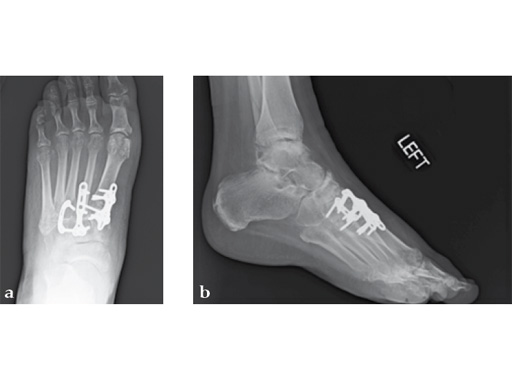

Fusion of the talonavicular joint while saving the rest of the hindfoot complex motion was achieved (see Fig. 4a-c).

Case 8: VA -locking X-plate

A 38-year-old man fell from a 7-foot height while at work. The patient was seen at an urgent care facility and diagnosed with an ankle sprain. He was placed in a stirrup brace and instructed to bear weight as tolerated.

Case provided by Michael Castro, Scottsdale, Arizona

After 4 months the patient presented for a second opinion. His complaint was pain to the lateral column and subtalar joint. The preoperative lateral x-ray is notable for a malunited talar neck fracture with subluxation of the subtalar joint. The disproportion of the medial and lateral columns and a cavovarus position of the foot are seen on both the AP and lateral views. The degenerative changes at both the talonavicular and subtalar joints are significant.

The patient was treated with arthrodesis of the talonavicular and subtalar joints. The compression/ distraction device was used to restore the length of the medial column. The articular surface of the subtalar joint was prepared arthroscopically. The talonavicular joint was debrided then packed with a tricalcium matrix. Length was maintained using a locking X-plate. The subtalar joint was then fixed with a 6.5 mm headless compression screw.

The patient returned to work 3 months after surgery. He wears an ankle brace when on uneven surfaces. His lateral column and subtalar pain have resolved.